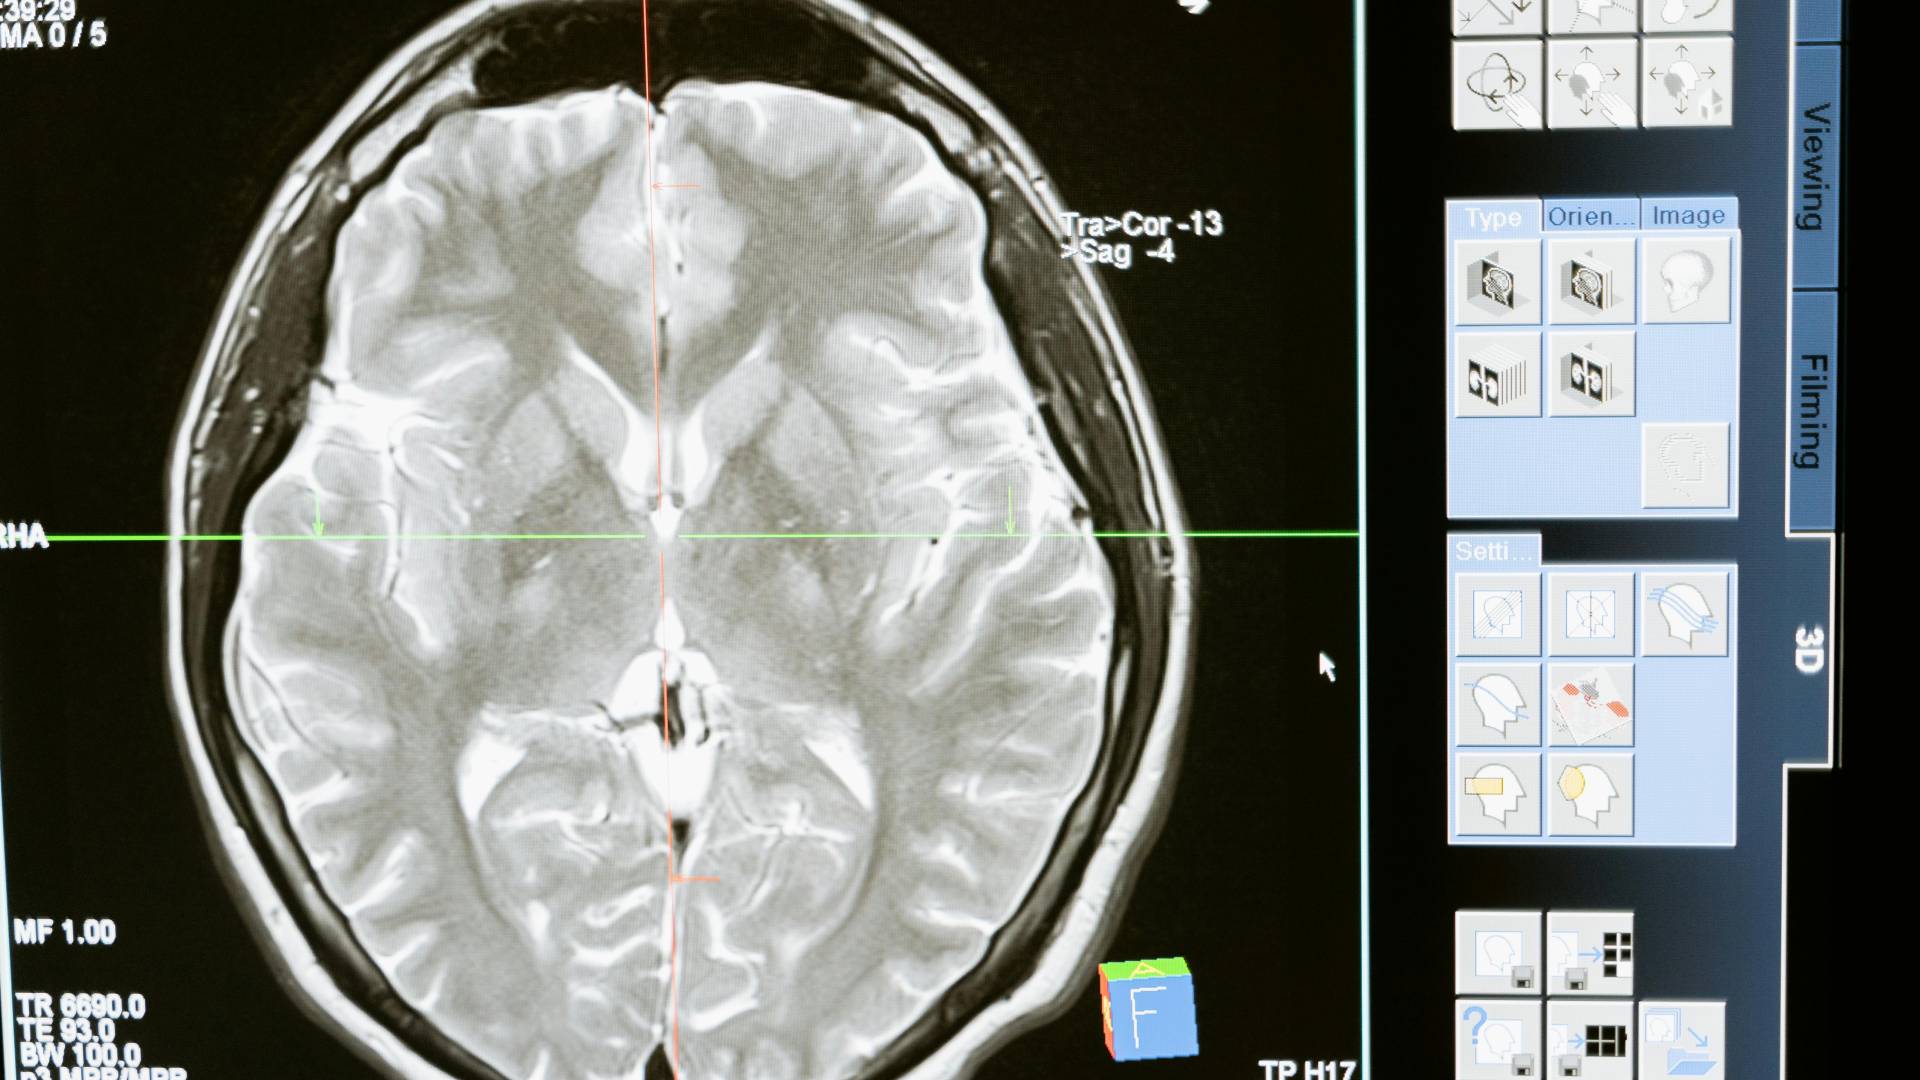

Podjetje Neuralink je prvič vstavilo možganski vsadek v človeka, je sporočil lastnik podjetja, ameriški milijarder Elon Musk. Dodal je, da so prvi rezultati obetavni.

Končni cilj podjetja je človeškim možganom s pomočjo vsadka omogočiti neposredno komunikacijo z računalniki in drugimi napravami.

Zagonsko podjetje Neuralink, ki ga je Musk soustanovil leta 2016, je maja lani dobilo dovoljenje za testiranje možganskih vsadkov na ljudeh, potem ko so ga najprej preizkusili na opicah. Implantat ima 1024 elektrod, ki jih robot z izjemno tanko iglo poveže s človekovimi možgani, poročajo tuje tiskovne agencije.

Možganski vsadek beleži živčno aktivnost in informacije posreduje v napravo, kot je pametni telefon. V zadnjem koraku naj bi ljudem omogočil upravljanje pametnega telefona in drugih tehnologij z mislimi.